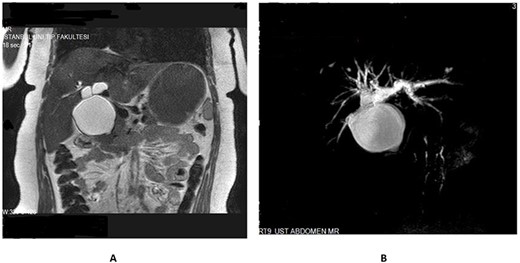

A 35-year-old female presented to a local hospital with a 3-month history of intermittent abdominal pain. Initial abdominal ultrasonography revealed cystic dilatation of the extrahepatic bile duct. A suspicion of choledochal cyst was made and was referred for surgical management. Her past medical history was unremarkable. She weighed 83 kg and was 164 cm tall, with body mass index of 30.9 kg/m2. Apart from mild right upper quadrant tenderness, her physical examination was unremarkable. Laboratory tests including liver and renal function tests, serum and urine amylase levels were normal. A magnetic resonance cholangio-pancreatography (MRCP) done showed a cystic fusiform dilatation of the common bile duct (CBD) extending into the right and left hepatic ducts (Fig. 1). No PBM was observed. The MRCP findings suggested type Ic CC. Without any further imaging, patient was scheduled for complete cyst excision with cholecystectomy and hepaticoenterostomy surgery. At laparotomy, the CBD was found to be fusiformly dilated. Bile samples were taken from the cyst and the gallbladder (GB) for amylase level essays. The GB was dissected from the liver bed and the cystic duct opened into the midportion of the cyst. After careful dissected of the cyst from surrounding vascular structures, the distal part entering the head of pancreas was noticed to be unaffected (Fig. 2). The distal part was transected just at the level of the head of pancreas and samples were taken for frozen section. Dissection at the hepatic hilum revealed two separate dilated ducts originating from the confluence of the left and right hepatic ducts and both entering into the cyst (Fig. 3). The two ducts were transected just distal to their origin from hepatic confluence to avoid confusing them as true right and left hepatic ducts (Fig. 4). The hepatic confluence was then opened to expose the true left and right hepatic ducts (Fig. 5). The dilated portions of the both hepatic ducts were transected and samples were taken for frozen section. A right and left hepaticojejunostomy reconstruction was done. No intraoperative cholangiogram was performed. Frozen section results of both the distal and proximal surgical margins were negative for malignancy. The amylase levels of both the cyst and GB were 47 031 and 44 770 U/L, respectively (normal serum amylase level: 25–110 U/L). Patient was discharged on postoperative Day 6. She is well with no evidence of malignancy after 23 months of follow-up.

(A) MRI and (B) MRCP showing cystic dilatation of the common bile duct with intrahepatic extension (type Ic).